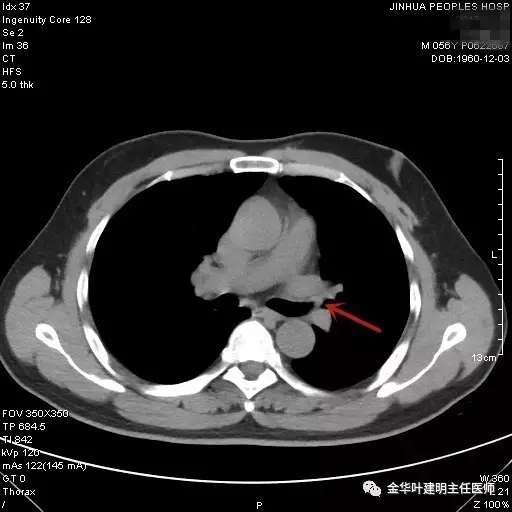

图一:红色箭头所指处示左肺上叶开口处的病灶,不仔细看根本发现不了,也极易漏掉

图二示:纵隔窗左肺上叶开口处新生物,相对肺窗稍明显